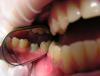

UnI Опубликовано 7 декабря, 2012 Поделиться Опубликовано 7 декабря, 2012 (изменено) а можете сказать какое основание под них? и как вы это делаете? ДЦ вклеивается на титановую платформу http://s020.radikal.ru/i720/1212/20/23614a7d16b0.jpg http://s59.radikal.ru/i165/1212/3f/2e9bc626f98b.jpg Изменено 7 декабря, 2012 пользователем UnI Ссылка на комментарий

Rtov Опубликовано 7 декабря, 2012 Поделиться Опубликовано 7 декабря, 2012 1.Снимаю слепок альгинатом для изготовления индивидуальной ложки;2.сниммаю слепок при помощи индивидуальной ложки с уровня имплантата с помощью трансфера для открытой ложки(масса IMPREGUM-полиэфир);3.покупается платформа(смотря какой имплантат был установлен), в лаборатории моделируют из воска будующий абатмен,фререруют,приклеивают его к платформе и...4. И Вуа ля))) Ссылка на комментарий